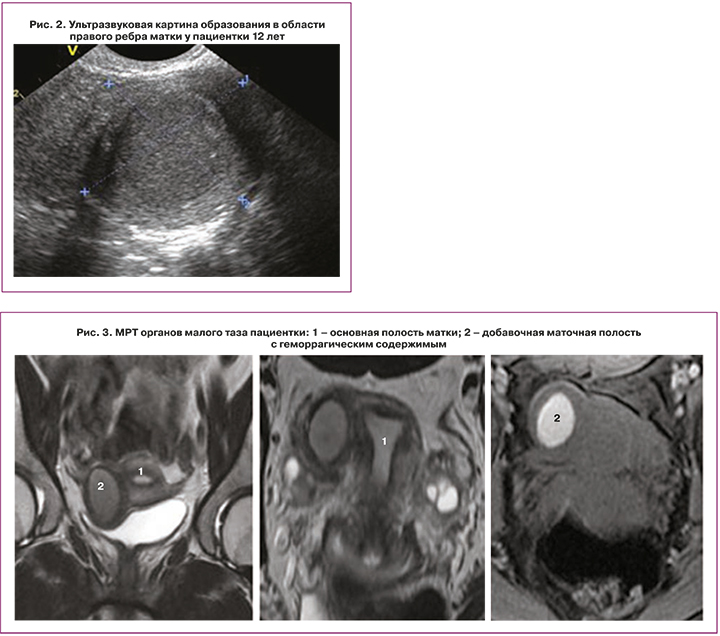

По данным УЗИ органов малого таза (рис. 2) матка расположена срединно, положение anteflexio, контуры ровные, четкие. Размер тела матки составляет 38×29×32 мм, шейки – 30×27 мм. Шеечно-маточный угол выражен. Эхо-структура миометрия не изменена. Эндометрий 7,5 мм, однородный. Яичники расположены в углах матки. Правый яичник размерами 35×17×24 мм, V=7,5 см3, эхо-структура не изменена, содержит фолликулы диаметром 7–8 мм, а также кистозную структуру округлой формы 19х15 мм с однородным мелкодисперсным изоэхогенным аваскулярным содержимым. Левый яичник размерами 26×17×21 мм, V=4,86 см3, эхо-структура не изменена, содержит фолликулы диаметром 5-7 мм, 6–8 в срезе. К правому ребру матки интимно прилежит образование округлой формы, диаметром 55×37×35 мм, с утолщенной до 6,2 мм изоэхогенной стенкой и полостью до 28 мм в диаметре с достаточно однородным содержимым. Эхографическое заключение: Эхо-картина функционирующей двурогой матки с замкнутым рогом справа. Эндометриоидная киста яичника справа.

По данным МРТ (рис. 3) органов малого таза визуализировано объемное образование 5–6 см в диаметре с полостью в области правого ребра матки, не сообщающееся с полостью матки, наиболее соответствует ACUM, следует дифференцировать с кистозным очагом аденомиоза. Кроме того, обнаружено кистозное включение в правом яичнике 1,5 см в диаметре, которое наиболее соответствует кисте желтого тела с кровоизлиянием.